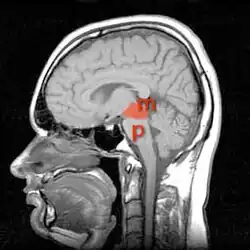

Кровоснабжение ствола головного мозга

Средний мозг на МРТ (отмечен красным), а мост буквой Р(pons)